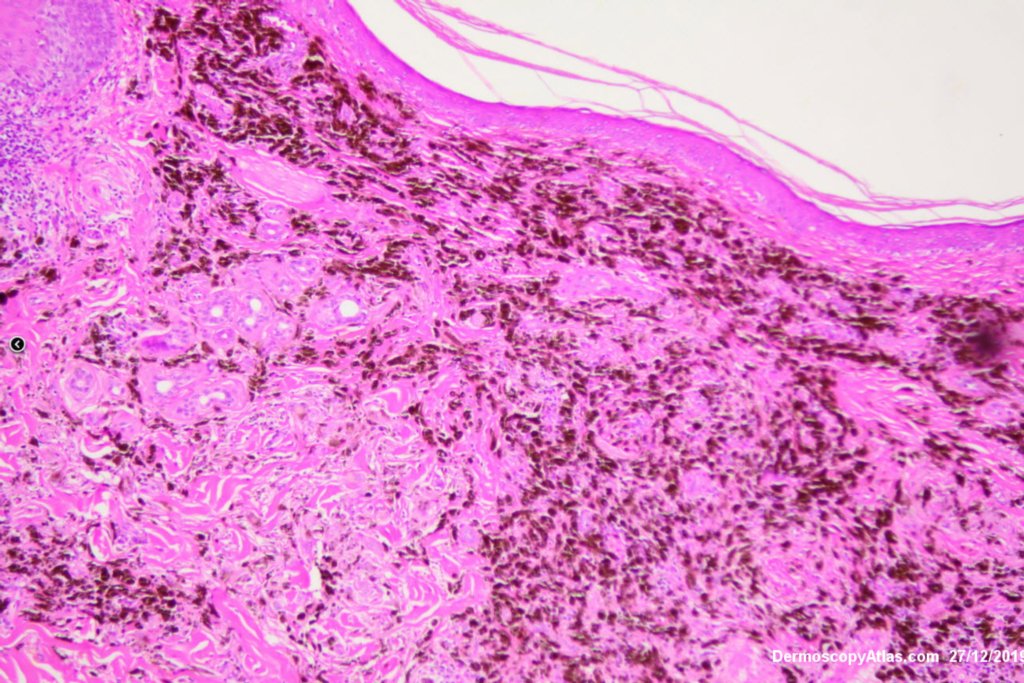

Diagnosis: Melanoma metastases

This elderly man had a preceeding lentigo maligna but subsequently developed in transit metastases as shown by the blue macules and papules on his cheek. He was treated with Keytruda. PET scan was negative for spread elsewhere.

It is important to treat lentigo maligna early to stop a situation like this from developing.